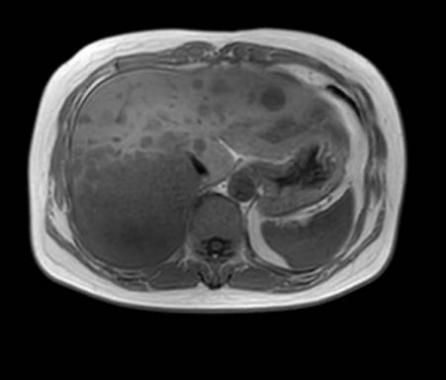

近日,哈医大肿瘤医院胸部放疗四病房尹航教授团队运用前沿空间分割放疗(SFRT)技术,成功为一名胸腺恶性肿瘤肝转移患者实施精准治疗。患者肝脏转移瘤直径由12cm显著缩小至 4.3cm,症状全面缓解,生活质量大幅提升,充分展现SFRT技术在晚期肿瘤治疗领域的突出优势和临床价值。

治疗期间,患者肝脏转移瘤从12cm迅速缩小至7cm,体积锐减超四成。治疗后3个月复查,巨大转移瘤已缩小至4.3cm,体积缩减近三分之二,患者生化指标大幅好转,体重较治疗前显著增加,疼痛症状完全缓解,饮食、睡眠与日常活动逐步恢复正常,生活质量显著提升。

左:治疗前 中:治疗中 右:治疗后三个月